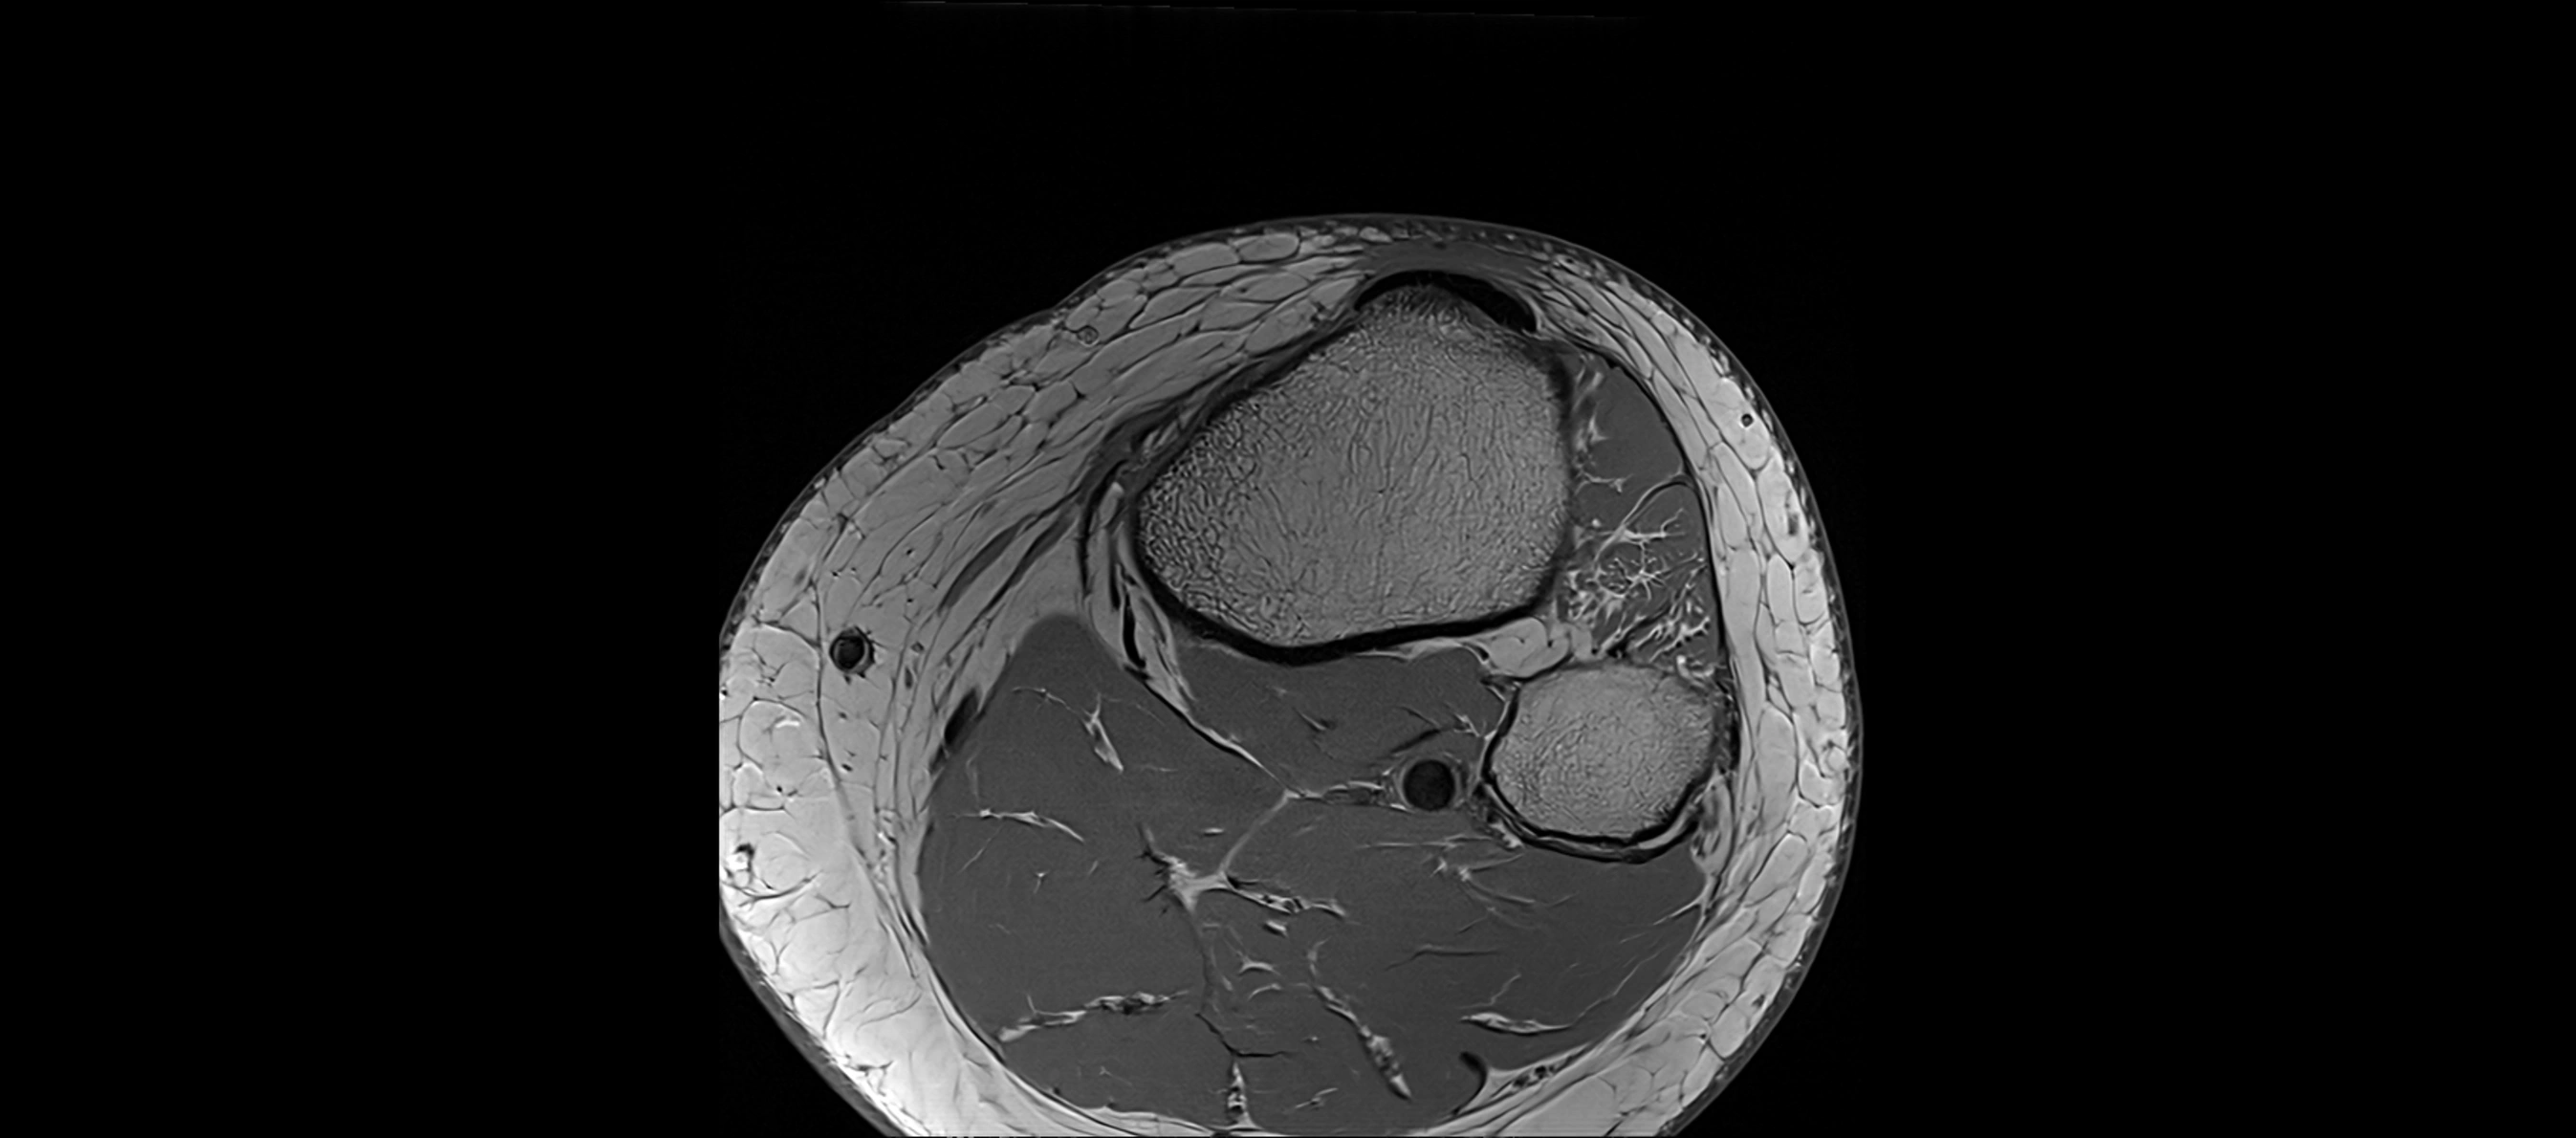

MRI images

image